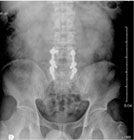

척추관 협착증의 방사선 소견